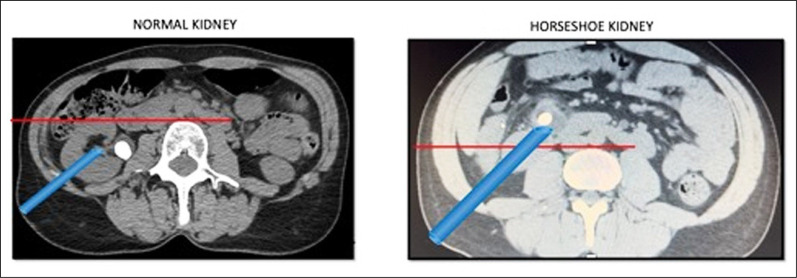

Introduction: Historically, percutaneous nephrolithotomy (PCNL) in horseshoe kidney (HSK) patients has been performed in the prone position. Nevertheless, thanks to the spread of the supine PCNL technique for patients with urinary stones and normal renal anatomy, some retrospective studies have already reported on supine PCNL and HSK, showing the effectiveness and safety of the procedure. Herein we report our experience with supine PCNL in a subset of patients with urolithiasis.

Material and methods: Prospective data were collected for all HSK patients who underwent supine PCNL at our institution from June 2016 to June 2023. Stone volume was reported as the volume of a single stone or the sum of the volumes of multiple stones on computed tomography (CT) images. Patients were reported to be stone-free if there were no stones on postoperative non-contrast CT (NCCT) exam. Peri-/postoperative complications were reported according to the Clavien-Dindo classification system. The primary endpoint of the study was stone-free rate (SFR) and the secondary endpoints were Clavien-Dindo complications Grade I or higher.